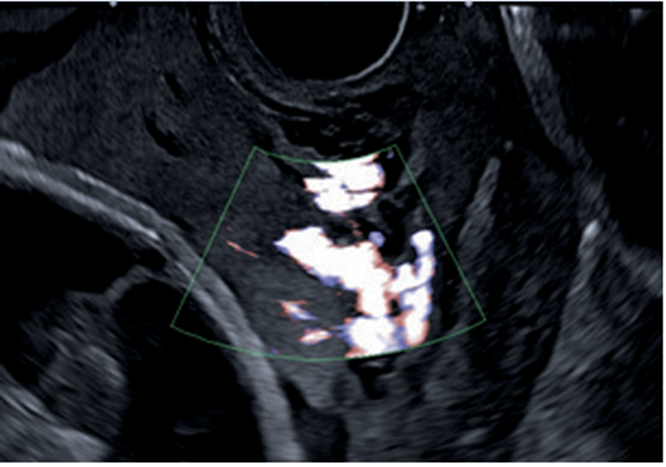

La paciente es valorada inicialmente por la Unidad de Diagnóstico Prenatal del Centro Hospitalario Pereira Rossell, donde cursando un embarazo de 31 semanas de edad gestacional, se realiza la sospecha diagnóstica de acretismo placentario. Se destaca de las imágenes elementos característicos de acretismo, como son, placenta previa oclusiva total con un aumento de su vascularización, pérdida de área hipoecoica retroplacentaria, abundantes lagunas placentarias y pérdida de diferenciación con miometrio en área del segmento (figura 1,figura 2,figura 3).